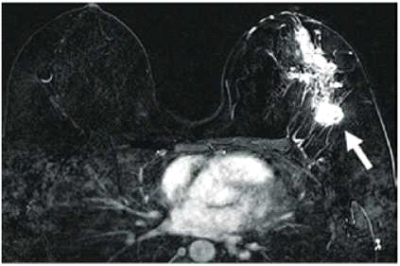

בדיקת MRI מאבחנת מוקדי מחלה נוספים, בקרב למעלה מ-15% מהנשים שחלו בסרטן השד ואובחנו באמצעות בדיקת ממוגרפיה או בדיקת אולטרסאונד - ולפיכך היא מגדירה את היקף המחלה בצורה מדויקת יותר בהשוואה לממוגרפיה ולאולטרסאונד בכ-15% הממקרים. בעקבות הממצאים שנראים בבדיקת ה-MRI, תוכנית הטיפול משתנה אצל כ-10% מהנשים[4] (תמונה מספר 2 א-ג).